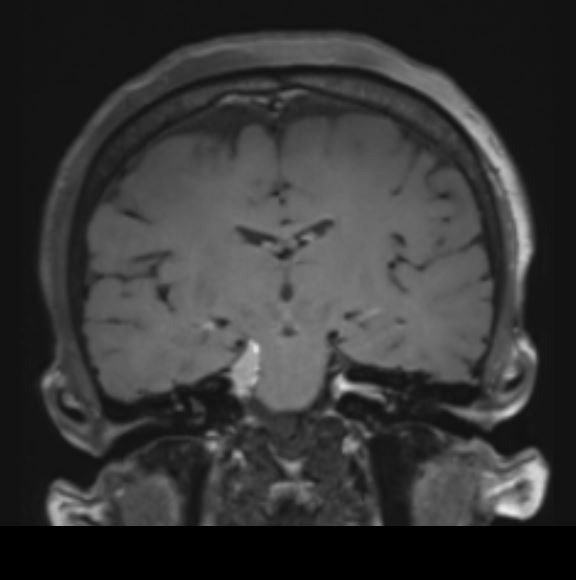

Η μαγνητική έδειξε ένα σχετικά μικρό ακουστικό νευρίνωμα αριστερά όμως η αιτία των προβλημάτων της ασθενούς ήταν ένα μηνιγγίωμα στην περιοχή της κορυφής του λιθοειδούς δεξιά το οποίο πίεζε το τρίδυμο νεύρο τόσο πριν όσο και εντός του Meckel’s cave (περιοχή του γαγγλίου του τριδύμου).

Αποφασίστηκε αρχικά η ακτινοχειρουργική αντιμετώπιση του ακουστικού νευρινώματος με ακτινοχειρουργική (SRS). Λίγες εβδομάδες μετά η ασθενής υπεβλήθη σε τροποποιημένη οπισθομαστοειδική κρανιοτομία (RISA – Retrosigmoid Intradural Suprameatal Approach) όπου η βλάβη αφαιρέθηκε ολικώς.

Η μετεγχειρητική μαγνητική τομογραφία ανέδειξε πλήρη εξαίρεση του όγκου (βλ εικόνες).

Η ασθενής είχε στην ουσία δύο όγκους: ένα ακουστικό νευρίνωμα (αιθουσαίο σβάννωμα) αριστερά και ένα μηνιγγίωμα σε μια ιδιαίτερα δύσκολα προσβάσιμη περιοχή του εγκεφάλου που λέγεται κορυφή του λιθοειδούς οστού (petrous apex) δεξιά.

Το μεγαλύτερο τμήμα του όγκου προσπελάσθηκε μέσω μιας τυπικής οπισθοσιγμοειδικής κρανιοτομίας όμως πρόβλημα αποτελούσε το τμήμα του όγκου το οποίο επεκτείνονταν στην περιοχή του γαγγλίου. Προκειμένω να αφαιρεθεί και αυτό το κομμάτι του όγκου “ανοίξαμε” την κορυφή του λιθοειδούς αφαιρώντας το οστικό έπαρμα ύπερθεν του εσω ακουστικού πόρου, μια απαιτητική και ιδιαιτερη τεχνική. Έτσι καταφέραμε την ολική εξαίρεση της βλάβης και την απαλλαγή της ασθενούς από τα συμπτώματά της.